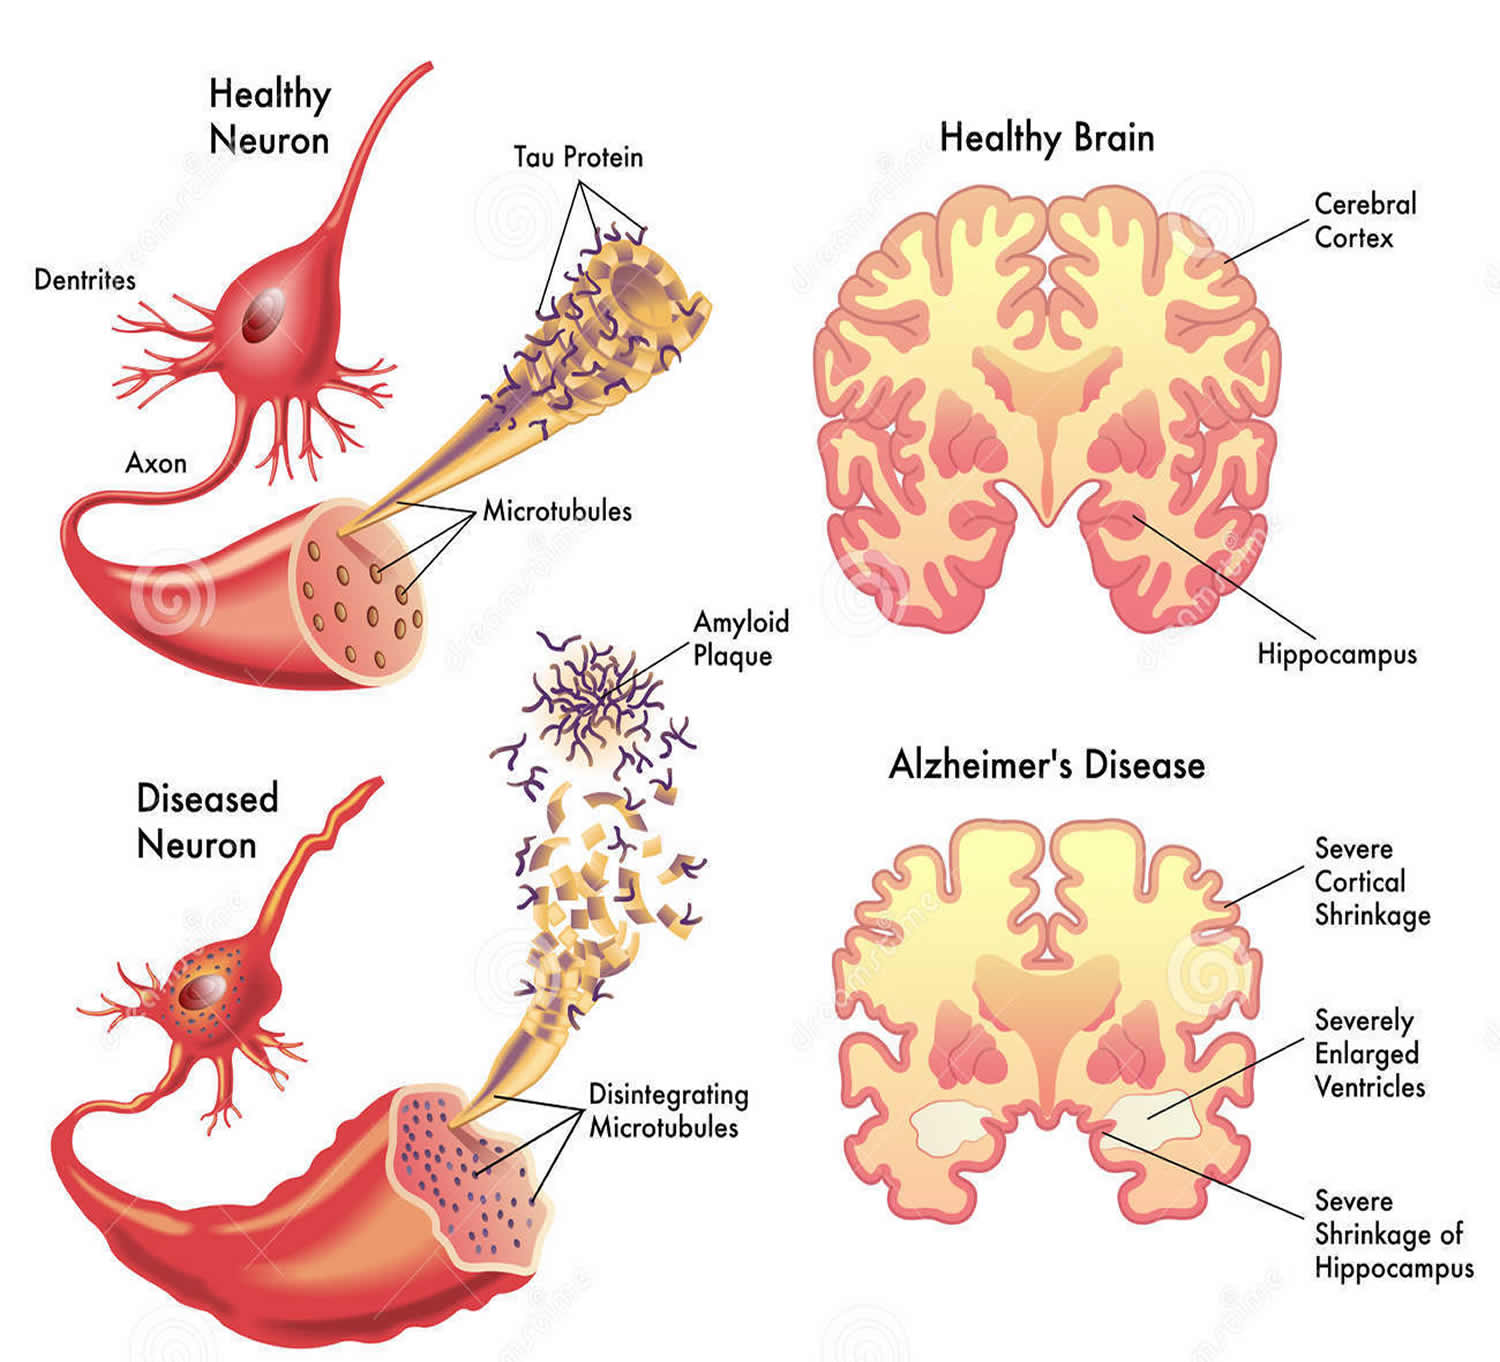

The Healthy Brain (left) and the Alzheimer’s Brain (right) | Download …

Nervous system: Alzheimer’s Disease and Strokes – Classroom Partners

Why Do Ventricles Enlarged In Alzheimer’s – DementiaTalkClub.com

Cross-section of the Human Brain with Alzheimer`s Disease Stock Vector …